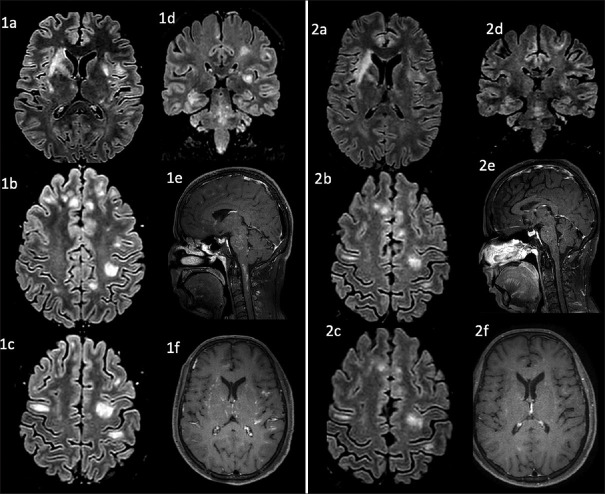

A Case of Supratentorial Lymphocytic Inflammation with Parenchymal Perivascular Enhancement Responsive to Steroids (SLIPPERS) with Associated Chronic Lymphocytic Inflammation with Pontine Perivascular Enhancement Responsive to Steroids (CLIPPERS) and a Review of Literature.